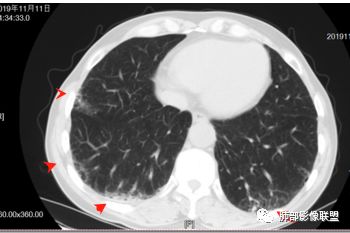

南边老师论述:    分叶凹陷的地方有血管,支气管进去,这个价值很大,后来引申到血管、支气管从凹陷的地方进去就叫脐凹征,就像番茄柄🍅,辣椒柄、苹果柄🍎一样的。后来就把这个做为脐凹征,95%以上的特异性。如下例:

后来发现胸膜牵拉,由远端凹陷的地方进去,他的价值也很大,诊断腺癌,几乎很少失误,后来把这个也纳入到脐凹征里。由凹陷处进入的胸膜牵拉征,由凹陷处进去的血管,都属于脐凹征。原理是由凹陷处进去的血管,因为肿瘤膨胀生长,生长过程中遇到血管,支气管区域受阻,边缘代偿性生长,膨胀的更厉害了,所以局部凹陷,前提是血管、支气管肯定在肺门侧,不会在远端有一条血管阻碍他的,可能性太小了。

脐凹征,支气管、血管引起的在肺门侧,因肿瘤生长在近端膨胀受阻的,病灶本身围绕支气管、血管周围包绕的不算,只有进去其中受阻的才算。